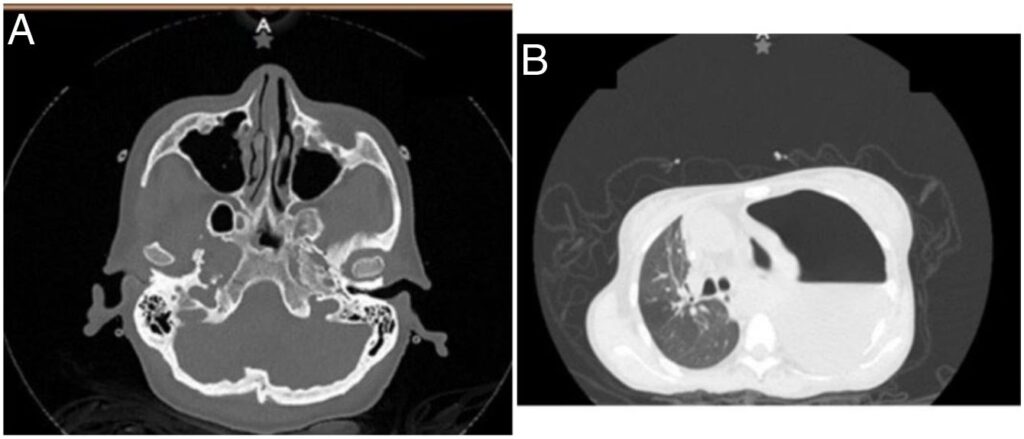

2. Billeddiagnostik: Et ekkokardiogram (ultralyd af hjertet) er det første og vigtigste skridt til at vurdere væske i hjertesækken, fortykkelse af perikardiet og hjertefunktionen. CT- og MR-scanninger kan give mere detaljerede billeder af perikardiets tykkelse og eventuelle forkalkninger.